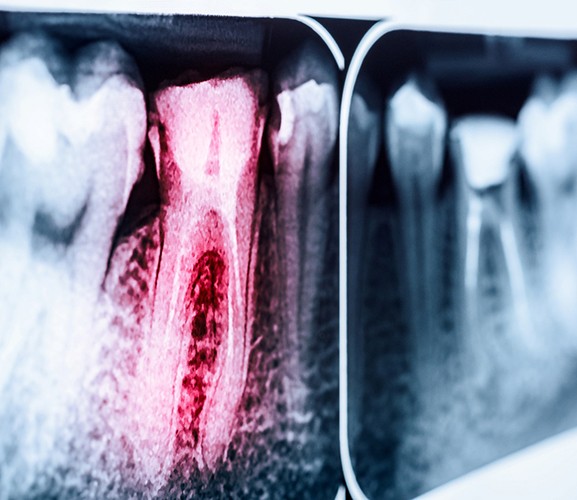

Root canal treatments are the best way to preserve a tooth that has become infected or suffers from extensive decay. Not only does this procedure remove the infection from the tooth and prevent it from spreading to other teeth and throughout the body, but it also allows you to preserve the tooth so you can continue using it, in most cases for the rest of your life.

If you have a tooth that is broken or that is suffering from an untreated cavity that has allowed harmful oral bacteria to access the sensitive inner pulp, you could benefit from a root canal.

First, your dentist will administer local anesthesia to the area, completely numbing it so you remain comfortable throughout the procedure. We also offer sedation options to help keep you calm if necessary. Once your mouth is numb, your dentist will use special, small instruments to remove the damaged pulp and fill the tooth with a special material called gutta percha. This supports the structure of the tooth and prevents future infections. Then, a crown will be placed over the tooth so that it looks and feels just like a natural tooth while preventing future bacteria from entering.